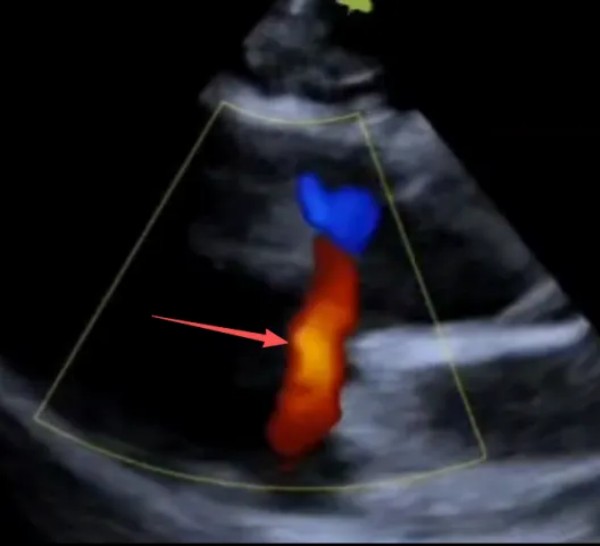

② 超声心动图:确诊金标准,通过二维超声可直接显示室间隔缺损的位置、大小;彩色多普勒超声可清晰观察分流方向与流速,同时评估心室壁厚度、肺动脉压力及瓣膜功能。

(视频内可见穿过室间隔出现红色血流,如图箭头所指,为靠近探头的方向,是左向右分流)